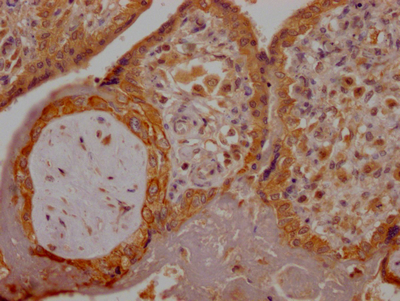

CSB-RA280380A0HU

IHC image of CSB-RA280380A0HU diluted at 1:100 and staining in paraffin-embedded human placenta tissue performed on a Leica BondTM system. After dewaxing and hydration, antigen retrieval was mediated by high pressure in a citrate buffer (pH 6.0). Section was blocked with 10% normal goat serum 30min at RT. Then primary antibody (1% BSA) was incubated at 4℃ overnight. The primary is detected by a Goat anti-rabbit IgG polymer labeled by HRP and visualized using 0.05% DAB.